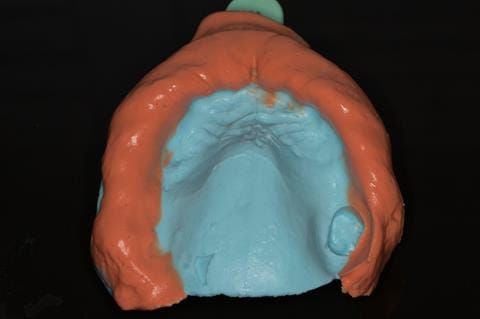

- Cobalt chromium reinforced gasket denture - using a Molloplast B "O" ring to retain and stabilise the denture. This was my professional preference as this was the least invasive and simplest solution to this dental problem. Should the UR7 require removal in the future - an artificial tooth could be added - resulting in a complete denture. The patient would have adapted to the denture fully by this stage and have good neuromuscular control of the prosthesis.

Following consultation and second discussion appointment the patient chose to have option 2 namely, a window denture - maxillary cobalt chromium based partial denture. The clinical situation and treatment process is shown in detail below with photographs. The patient was successfully rehabilitated with this and her quality of life considerably improved. The clinical work was provided by Finlay and the technical work by Rowan.